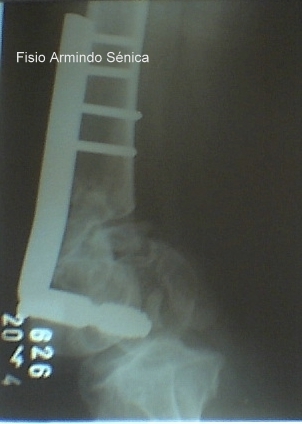

Fratura supra condiliana femur-pós cirurgico-Pino-placa tipo DCS

RESPONSÁVEL PELA REABILITAÇÃO: FISIOTERAPEUTA ARMINDO SÉNICA PERDIGÃO